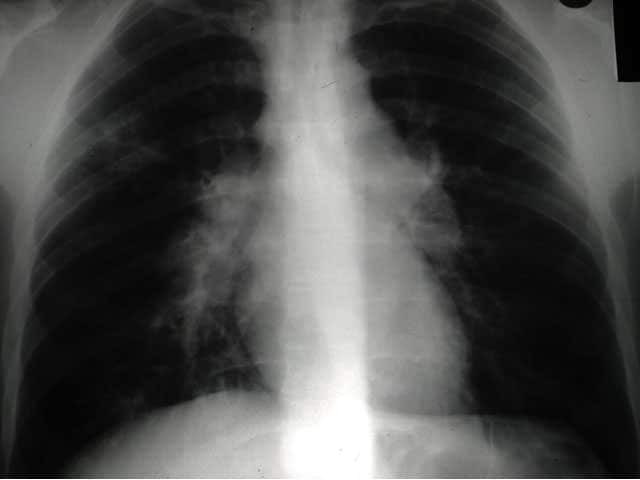

Bihilar lymphadenopathy in sarcoidosis